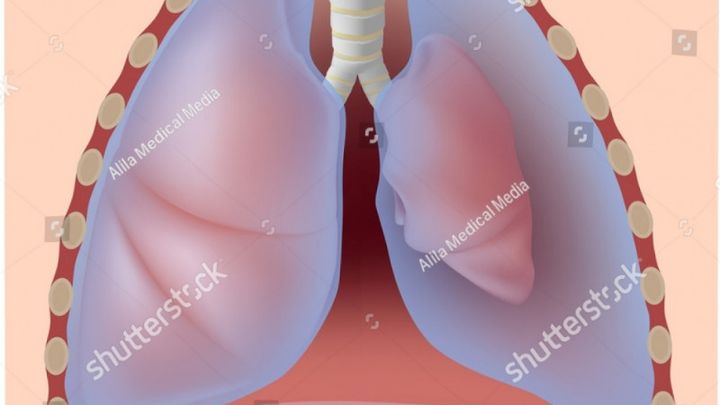

Hello. My name is Matthew, and my father is currently in the Intensive Care unit in Anderson Hospital. He has two collapsed lungs.

We started noticing problems two days ago, when he began complaining of shortness of breath. This came to a head last night (10/16) around midnight, when he tried to lay down. He became completely incapable of drawing a breath, and his skin was ice cold to the touch. We rushed him to the local ER, where he was diagnosed and a pair of tubes inserted between his ribs to alleviate some of the pressure on his lungs. He was sent from there to Anderson, where he is currently in ICU.

We started noticing problems two days ago, when he began complaining of shortness of breath. This came to a head last night (10/16) around midnight, when he tried to lay down. He became completely incapable of drawing a breath, and his skin was ice cold to the touch. We rushed him to the local ER, where he was diagnosed and a pair of tubes inserted between his ribs to alleviate some of the pressure on his lungs. He was sent from there to Anderson, where he is currently in ICU.